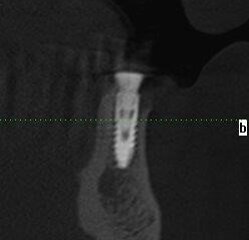

Planowanie nawigacyjne polega na wykonaniu zdjęcia CBCT, a następnie wprowadzeniu danych DICOM do programu nawigacyjnego oraz kolejno przyporządkowaniu krzywej panoramicznej do szczęki lub\i żuchwy. W żuchwie niezbędne jest wyznaczenie przebiegu nerwu zębodołowego dolnego, aby nie doszło do kolizji implantów z ważnymi strukturami anatomicznymi. W programie tym przeprowadza się wirtualny plan rozmieszczenia implantów, a następnie koron przyszłych zębów. Dzięki temu korony protetyczne można dopasować do sytuacji zgryzowej pacjenta oraz określić kątowość łączników.

Ponadto, istnieje możliwość zaplanowania, a tym samym wykonania uzupełnienia protetycznego tymczasowego, którym natychmiast po przeprowadzonym zabiegu implantacji pacjent zostaje zaopatrzony. W programie widać prawidłowe trójwymiarowe położenie wszystkich osi: osi implantu w wyrostku zębodołowym, osi implantu oraz osi przyszłej korony.